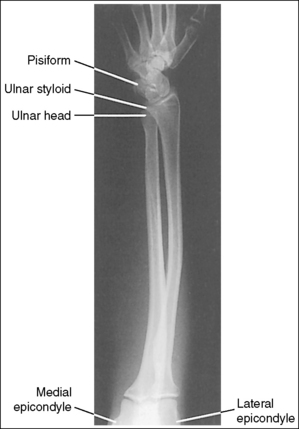

The distal and proximal forearm is positioned in an AP projection. The radial styloid is demonstrated in profile laterally, and superimposition of the metacarpal bases and of the radius and ulna is minimal.

The ulnar styloid is projected distally to the midline of the ulnar head.

The proximal forearm is positioned in an AP projection. The radial head is superimposed over the lateral aspect of the proximal ulna by approximately 0.25 inch (0.6 cm). If included on the IR, the medial and lateral humeral epicondyles are demonstrated in profile at the extreme medial and lateral edges of the distal humerus.

The radial tuberosity is demonstrated in profile medially, and the radius and ulna appear parallel.